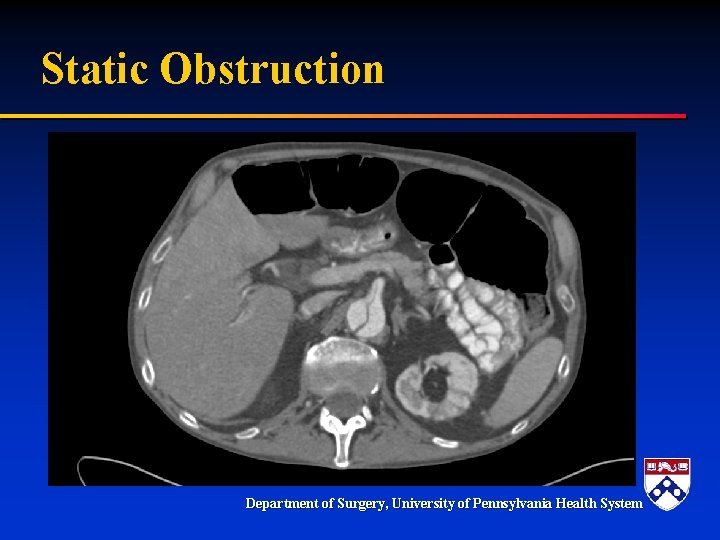

Acute Type B and Malperfusion Mechanism § Dynamic – – § Pressurization of false lumen and mobile dissection flap Leads to narrowing or occlusion of true lumen Dynamic process Degree of malperfusion relates to degree of compression Compromised perfusion to end organ Static – Dissection extends into branch vessel – Narrows branch vessel – Creates a fixed obstruction § Combination Department of Surgery, University of Pennsylvania Health System

Static Obstruction Department of Surgery, University of Pennsylvania Health System

Treatment § TEVAR – Seal entry tear – Expand true lumen-if necessary § Adjunctive stenting! Department of Surgery, University of Pennsylvania Health System